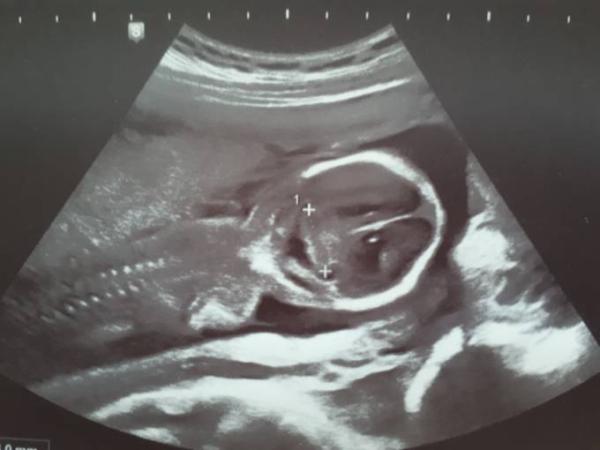

Hier geht's glaub ich. Da hat meiner auch keine arme und Beine.

Bild zu